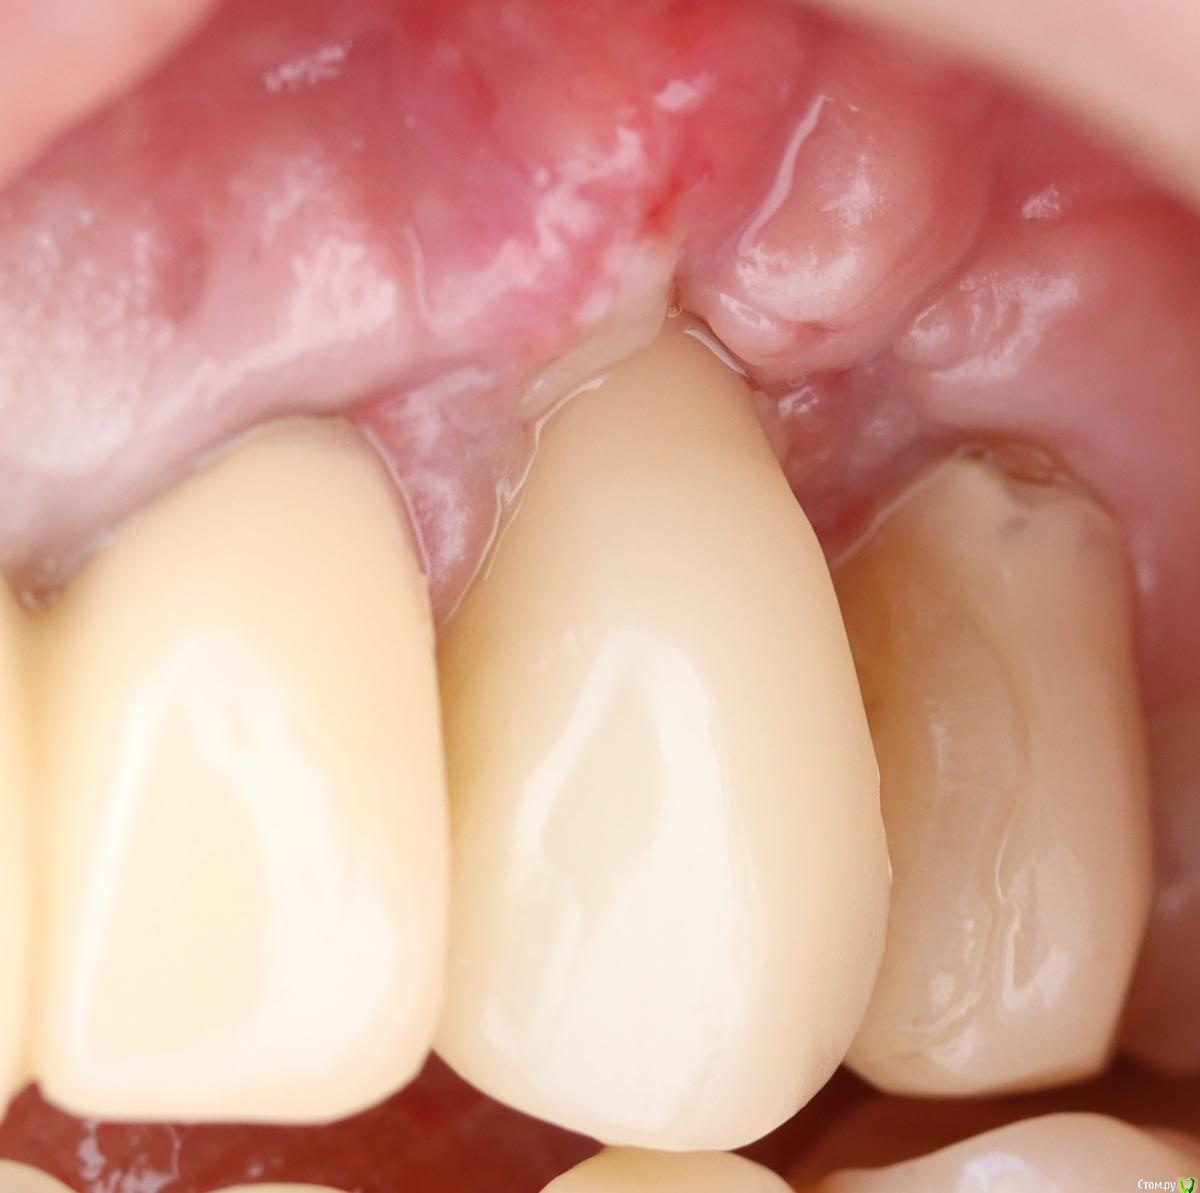

Doctor Vlad Опубликовано 2 февраля, 2021 Автор Поделиться Опубликовано 2 февраля, 2021 Ну как там дела? Я сегодня вспомнил Ваш случайОго,а я думал че икал вчера)) Она была на осмотре до нового года. В корональной части там где был пергамент по толщине я потерял. Но это и без операции ушло бы. Возможно это как-то связано с толщиной временной коронки. Я ее истончил, но не достаточно, на мой взгляд. Это к теме о поддержать протетикой. Отправил ее гулять на 2 месяца. потом думаю коронально смещать и еще добавлять. Чтобы высоту исправить. Ссылка на комментарий

Doctor Vlad Опубликовано 2 февраля, 2021 Автор Поделиться Опубликовано 2 февраля, 2021 здесь в корональной части получше, опять все гладилкой отслоили)? Ссылка на комментарий

колесников Опубликовано 2 февраля, 2021 Поделиться Опубликовано 2 февраля, 2021 Я же писал,гладилка,скальпель15С,пинцет-вот все что нужно для работы. Правда тут был перионож,под углом в шахту не удавалось войти.Все хорошо у Вас. Надо подождать. Я думаю подрастёт. И ещё добавить . Расщеплять будет уже веселее. Красивый профиль сделали на реставрации. Но! Этот уступ 1мм! Он все портит. Или пилить юбку или брать высотой 3мм Ссылка на комментарий

Doctor Vlad Опубликовано 15 февраля, 2022 Автор Поделиться Опубликовано 15 февраля, 2022 край десны через пару месяцев после пластики решил кровануть и воспалиться. он там остается очень тонким и видимо при чистке травмируется 1 Ссылка на комментарий